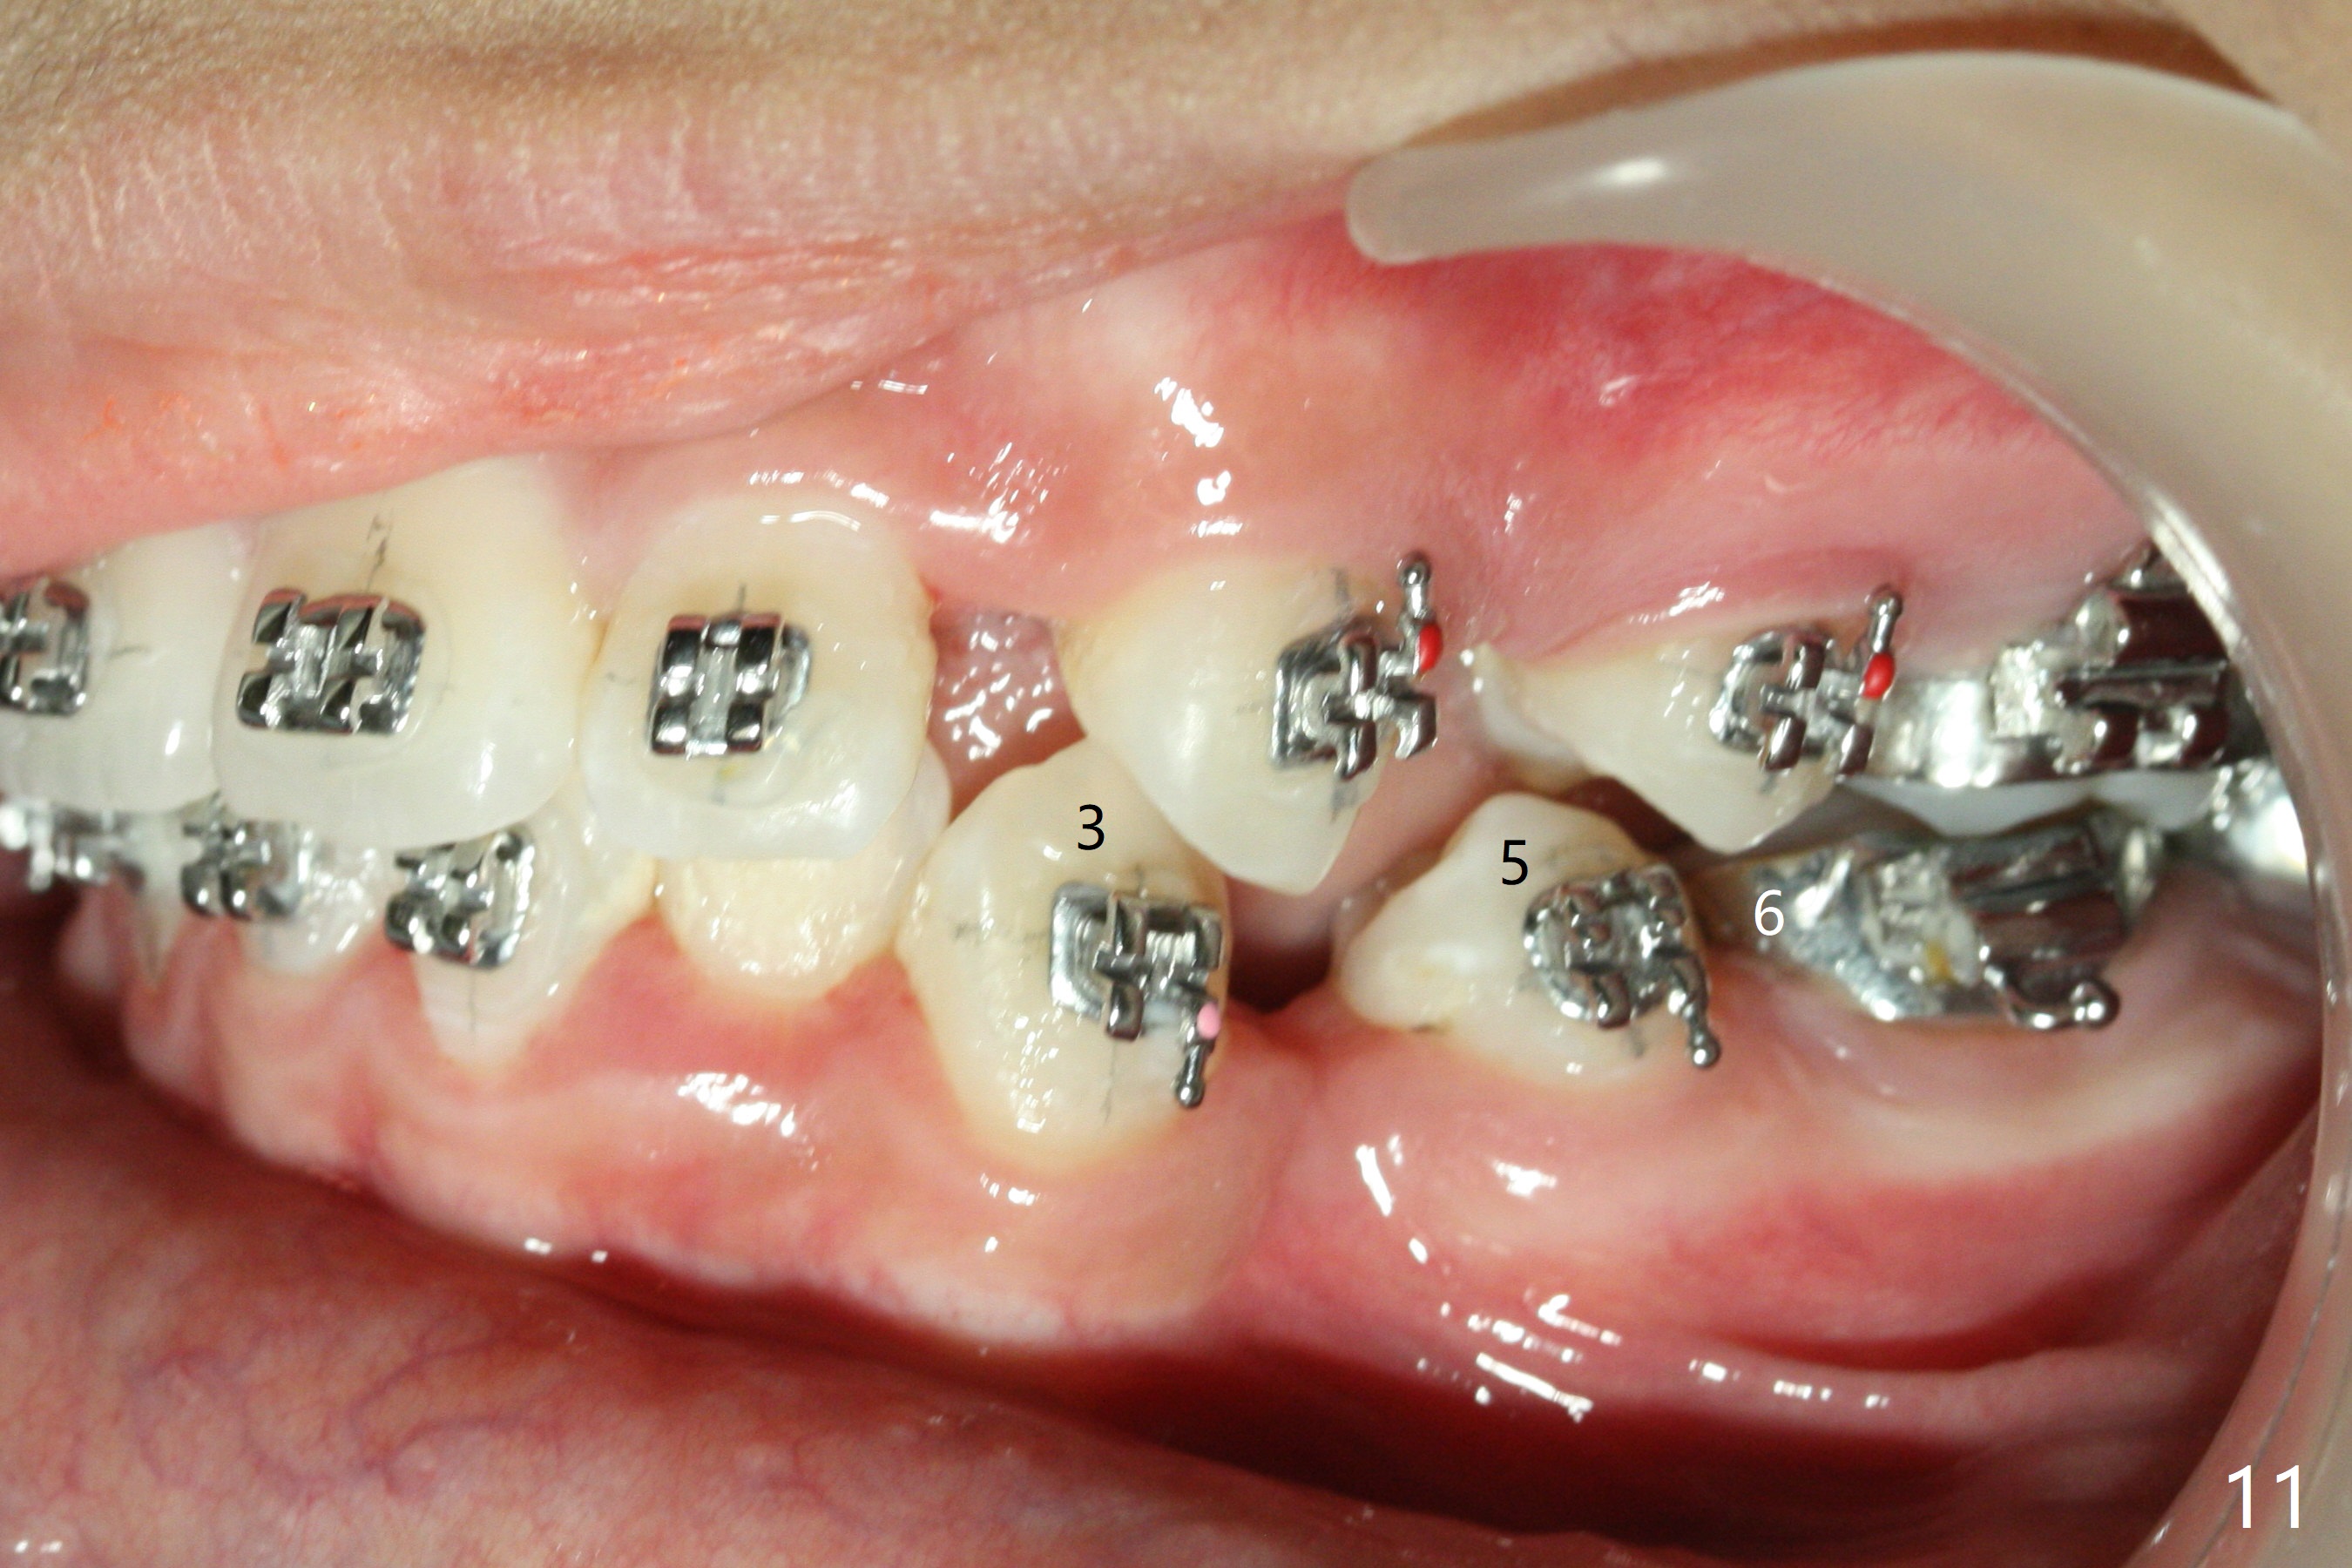

For the lower left quadrant, a band is placed at 7, but not at 6, since the space between 5 and 6 is not enough. A new separator is placed between 6 and 7, while power chains are placed between 3 and 5 (Fig.3). The patient will return for banding at 6 next week.

In fact there is enough space for banding at LL6 with reuse of 12 niti (Fig.4). Anterior crowding improves 1 month post banding (Fig.5, as compared to Fig.1-3); there is no difficulty in place 14 niti wire between UL 5 and 6 (Fig.6, as compared to Fig.3), since UL5 has been lingualzied.